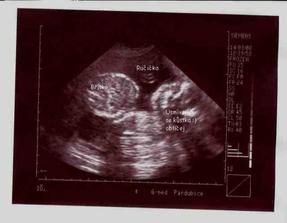

10.1.08 Další kontrola s ultrazvukem, miláček je krásně živej, všechno OK. 11.2.08 Kontrol proběhlo více, všechny víceméně v pořádku ... máme za sebou krevní testy, triple testy ... malý háček se objevil v maminčině krevní skupině rh- , ale snad bude vše v pořádku, testy na protilátky jsou negativní. Jinak mě začínají tlačit kalhoty, což asi znamená adios malému bříšku, ... welcome hrošíku 🙂 už přes týden cítím většinou večer malé motýlky a pomalu se vrhám na střádání výbavičky. Pěkně to utíká 🙂 7.3.08 Lékaři mě začínají trošičku děsit ... Prý jsme nějak menší, než je normální ... zhustila se frekvence prohlídek a hrozí mi kontrolka. 14.3.08 Screening ve 20 týdnu jsme absolvovali ve 21+1, jsme drobnější, ale jinak funguje vše, vše správně. Jen se nepodařilo odhalit, jestli Denis nebo Juli 🙂 24.4.08 3D utz v Hradci Králové, všichni byli milí, jen mrňousek bude prostě obrovskej stydlín ... ale pan doktor mi alespoň konečně prozradil, že to bude stydlivka Julinka 🙂 🙂 mám radost. A taky jsme se poprvé dozvěděli kolikvážíme ... celých 1060 gramů. 29.5. obvyklá prohlídka u gynekologa, už po dvou týdnech 🙂 Paní doktorka neustále straší, že mám malé bříško a poslala mě do nemocnice na dopllera. Mělo by to být vyšetření průchodnosti cév, prokrvení placenty. Pan doktor sice prohlásil, že Juli je menší, ale placenta je pěkná a mně už se mu nechtělo vyprávět příběh o cyklu s ovu 19DC a ne 14DC, jak mi neustále počítají ... Už se hodně informujeme o možnostech porodu a všeho okolo, říkám, už aby to bylo za námi a Julis s námi :D (ani jsem si na zprávě skoro nevšimla, že nás pan doktor vážil, takže 32+6 má Julísek krásných 2240 gramíků > pořád nechápu, co se jim nezdá :D 27.6.08 další dopller, paní doktorce se pořád nezdá moje bříško a tak zase víme, že už Juli váží 2770 gramíků, průchodnost cév je v pořádku a vše ostatní taky, bude to prostě cvrček majinkatej, vzali jsme to i s prvním monitorem a ten byl taky velice v pořádku ... tak ještě pár dní a už se setkáme 🙂 30.7.08 Jak jsem se bála, že nás budou nutit a teď bych nevím co dala za to, kdyby nastala nějaká změna. Přes týden přenášíme a malá se stále k ničemu nemá. Kontroly v nemocnici dvakrát do týdne už mě opravdu začínají otravovat. V pondělí jsem dokonce okusila Hamiltona, ale nijak zvlášť to nepůsobí. Tak už pojď ven mrško 🙂